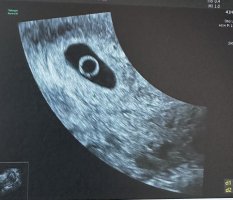

Jeg var endelig gravid igjen etter en MA i oktober, men fikk plutselig en blødning med smerter i dag 7+6. Har jobbet mye mentalt denne graviditeten for å komme meg til uke 8, da embryoet døde i uke 7 sist. Dro til gynekolog i kveld, og det viser seg at jeg har blighted ovum og at det aldri har vært et foster. Bare morkake og fostersekk. Skal på sykehuset i morgen tidlig for å få fortgang på prosessen med piller.